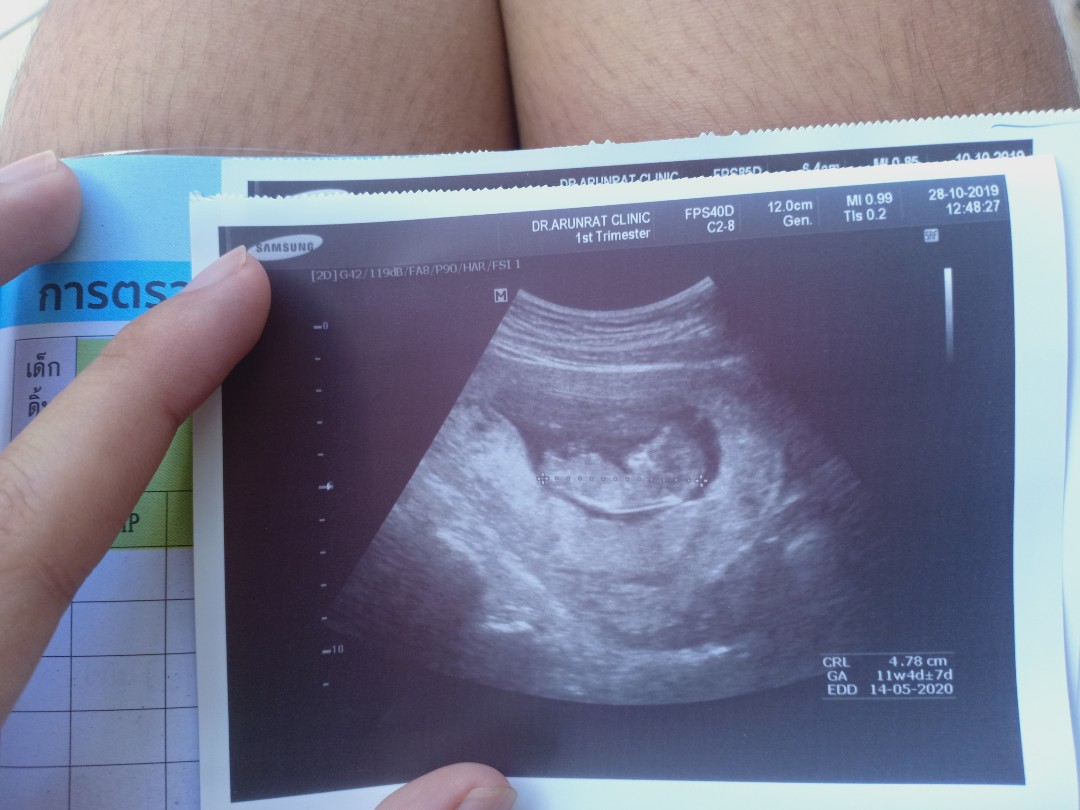

ขอถามเเม่ๆหน่อยค่ะอายุครรภ์ประมาณนี้สามารถซาวได้ยังค่ะจะเห็นร่างกายน้องไหม. ขอบคุนค่ะ

11w ค่ะ